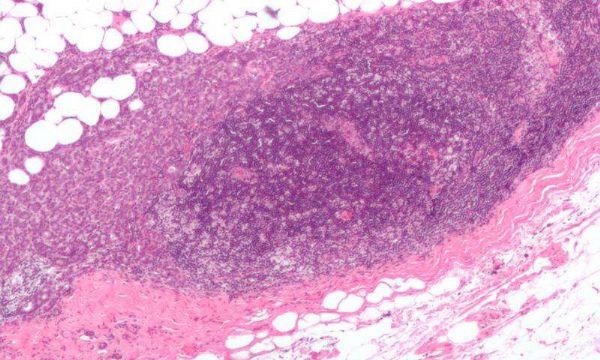

当细胞以异常高的速度增殖并在健康组织中聚集成团时就会形成肿瘤,而其中有一些细胞异常狡猾。“有时癌细胞会离开肿瘤组织传播到身体其他部位,这使得疾病的进展异常复杂。”IRCM细胞骨架组织和细胞迁移研究项目组长Côté说道。

这些细胞比其他细胞更容易迁移,它们会从肿瘤组织脱离进入血液并达到其他器官,例如肺、骨头或者大脑。这些所谓的“转移癌细胞”传播到其他组织后更难杀伤,也更耐受现有治疗方法,90%的乳腺癌患者死亡是由转移导致。因此肿瘤学研究中的一个重点就是防止肿瘤细胞转移,因为这可能救命。

Côté及其同事在防止转移的道路上又前进了一步。在他们的研究中,他们发现AXL这个蛋白质影响着HER2阳性的乳腺癌的转移。HER2阳性的乳腺癌中,AXL水平较高的细胞更可能从肿瘤组织中脱落发生转移。

这项研究在小鼠及癌症病人的肿瘤细胞样品中完成。关于病人的统计数据也很鼓舞人心。在HER2阳性的乳腺癌患者中,AXL水平越低,生存率越高。此前研究人员还将AXL与另一种癌症联系在了一起(

三阴性乳腺癌),但是没有人检测过它在HER2阳性的肿瘤组织中的情况。